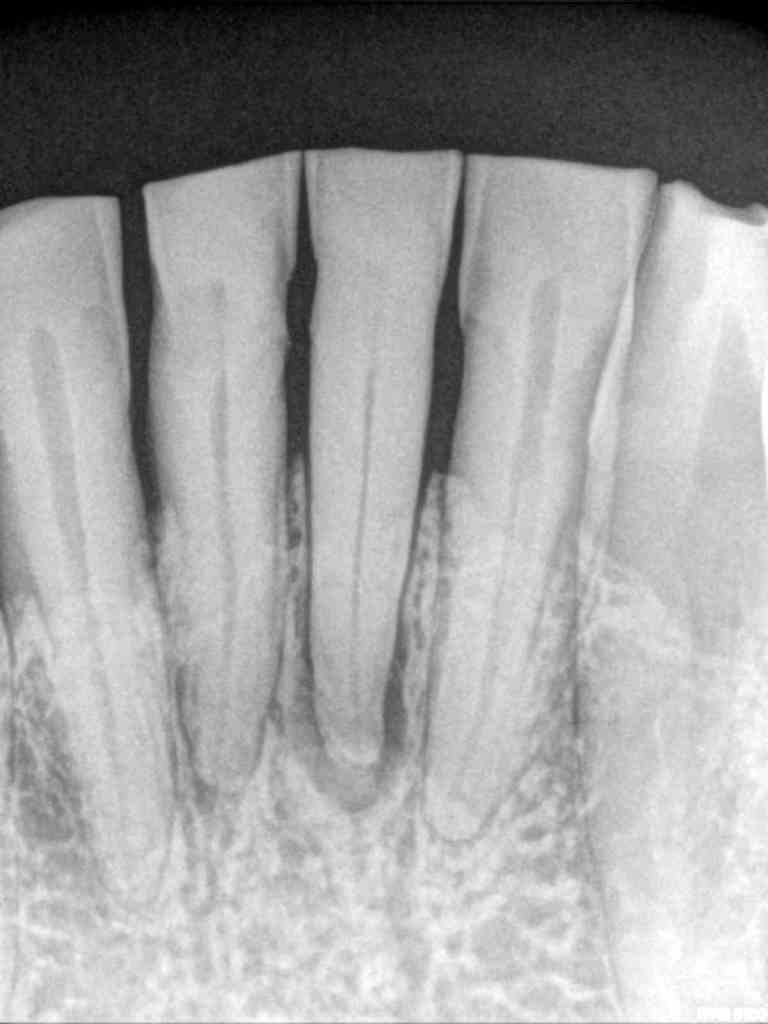

El paciente acude a la consulta en 2022 con sintomatología compatible con necrosis pulpar en el diente 3.1. Tras la confirmación diagnóstica, se realiza el tratamiento de conductos. Un año después, el diente 4.1 presenta un cuadro clínico similar, asociado a la sobrecarga funcional derivada del bruxismo. Se diagnostica necrosis pulpar y se procede igualmente a realizar tratamiento endodóntico. En 2025, el paciente acude con la presencia de una fístula vestibular a nivel del 4.1. Tras la evaluación clínica y radiográfica, se concluye la existencia de una fractura radicular vertical, lo que compromete el pronóstico del diente (Figuras 1-6).